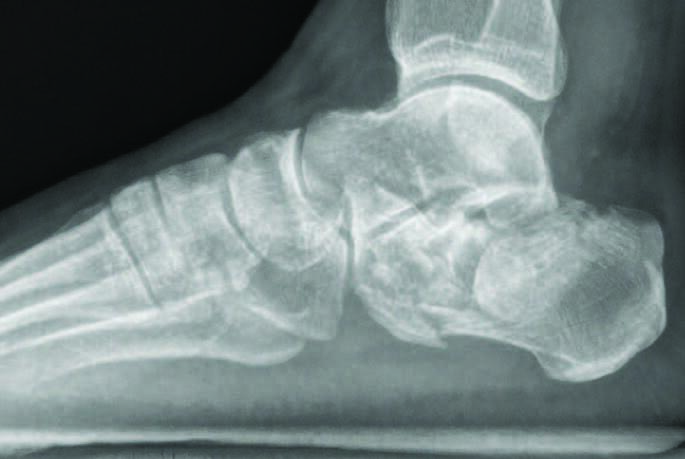

A Closer Look At Calcaneus Fractures

Injuries resulting in calcaneal fractures are usually high velocity in nature and are associated with proximal polytrauma. The fractures in the calcaneus seen from these types of injuries are oftentimes multiple and result in lateral wall blowout. Due to the forces seen in these injuries further soft tissue injury from surgery is a concern. The main goals in reducing calcaneal fractures are to maintain the height and length of the calcaneus, and to preserve as much of the STJ articulation as possible in proper alignment. This can be facilitated through Schantz or Steinmann pins into the calcaneal tubercle placed percutaneously to restore the height and length through manual traction. The basic minimal incision approach to calcaneal fractures entails a sinus tarsi approach instead of a large lateral extensile incision. Further reduction of the anterior process, and posterior facet of the STJ articulation can be achieved through percutaneous K-wire fixation from the lateral wall and incorporating the sustentaculum tali medially. The calcaneal plate can be introduced in much the same manner as the MIPO technique seen in pilon fractures. The main incision is usually placed lateral to the Achilles tendon insertion with the length that allows full introduction of the calcaneal plate. Posterior screw fixation can be introduced through this larger incision. Two minimal incisions can often times be utilized to place the remaining anterior and middle cluster of screws. The final reduction and fixation are checked under fluoroscopy before closure. Long-term data of percutaneous calcaneal fracture fixation of Sanders II and III fractures at 16 years shows ‘essentially normal’ function.12 Arthroscopic debridement is oft employed here to facilitate reduction and confirmation of joint surface restoration. The authors typically advocate for a sinus tarsi approach with plate/screw fixation with a final arthroscopic confirmation of fracture reduction at closure.